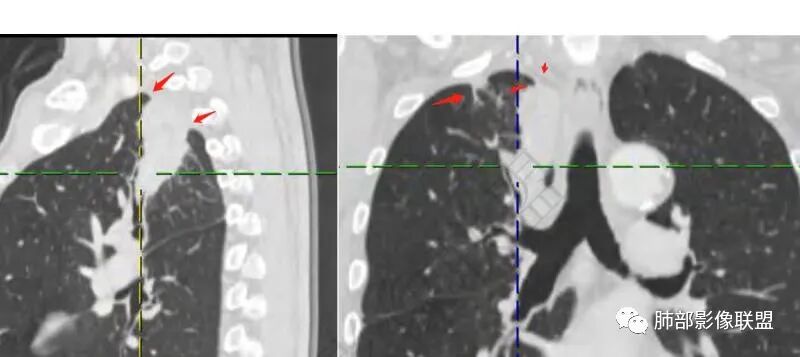

红星:老年男性患者有长期的吸烟的病史,临床症状是干咳。影像学表现右上肺胸膜下的分叶状的结节,密度欠均,内部见小灶性的坏死以及支气管空泡征,增强扫描呈明显的强化,从重建的图像来看,病灶的上下径较长,并沿着支气管的长轴生长,纵隔内无明显的肿大淋巴结。考虑肉芽肿性病变,结核性病变?炎性?鉴别诊断:肺鳞癌。

放射线:右肺尖不规则肿块,有分叶毛刺,有胸膜栽赃,冠状位可见支气管粘液栓,矢状位病灶呈外朝内沿支气管分叉角生长,强化明显,考虑腺癌,鉴别炎性肉芽肿病变。

良孑:右上肺占位,有平直及u型凹陷,其内见粘液拴及虫蚀样坏死空洞,不均匀强化,坏死空洞环状强化,失状位病灶沿支气管长轴生长呈爬行征样改变,综合考虑为炎性肉芽肿,首选TB,鉴别诊断鳞癌

琦遇:病灶沿右肺上叶尖段走形实变,远端大近端小,边缘平直收缩为主,近端尖段分支部分截断,内部可见扩张的支气管粘液栓,增强后明显强化,比较均匀,内部血管走形自然,与纵膈胸膜及后胸膜呈糊墙样,未见栽桩,纵膈未见明显肿大淋巴结 综合分析考虑炎性病灶可能性大 (IMT、OP、结核、慢性炎症) 因患者年龄大、老烟民 警惕恶性可能(淋巴瘤、鳞癌) 临床上下一步做支气管镜看看

张延军:右肺上叶条片影,边缘以平直及凹陷为主,病灶内见管状低密度影,延迟后边缘有强化,近段气管截断,血管走形自然,整体外宽内窄,考虑炎性肉芽肿,结核不除外

外围大、内带小,宽基底与胸膜相连,附近卫星灶

支气管进入病灶内,广泛胸膜增厚

支气管粘液栓

支气管堵了,但是远端粘液栓:是粘液栓堵塞?还是狭窄或堵塞后继发粘液栓?

病灶是支气管腔内堵塞导致远端实变、不张?还是外围病灶融合、实变影响近端支气管?

现有的图显示近端支气管还是连续的,只是远端扩张,腔内粘液栓,其实还应当看重建的支气管连续的图,与近端含气部分的连续